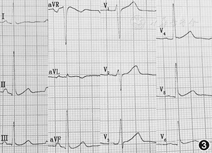

患者于2015年5月21日在局麻下行心内电生理检查和射频消融手术,术中证实存在2条旁路,1条位于右侧游离壁,另1条位于左后侧壁,射频消融术后观察15 min重复电生理检查旁路未恢复,无心动过速复发,手术成功,术后心电图示正常(图3)。